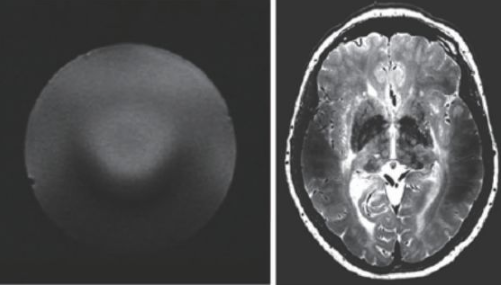

超高場MRI的射頻場設計也是一個較為困難的問題。由于射頻頻率超過了300 MHz,介電常數引起的問題非常突出。圖13 是一個在7 T 下的成像結果,可以看到在圖像內部的信號非常不均勻,由于射頻波長的極度縮短,組織的介電常數對射頻場的分布有極大的影響,這也是目前超高場MRI 需要解決的重要問題之一。目前的9.4 T以上的MRI設備還難以獲得人體體部掃描的良好圖像,其主要應用還是做頭部的掃描。

圖13 超高場下的射頻場不均勻性